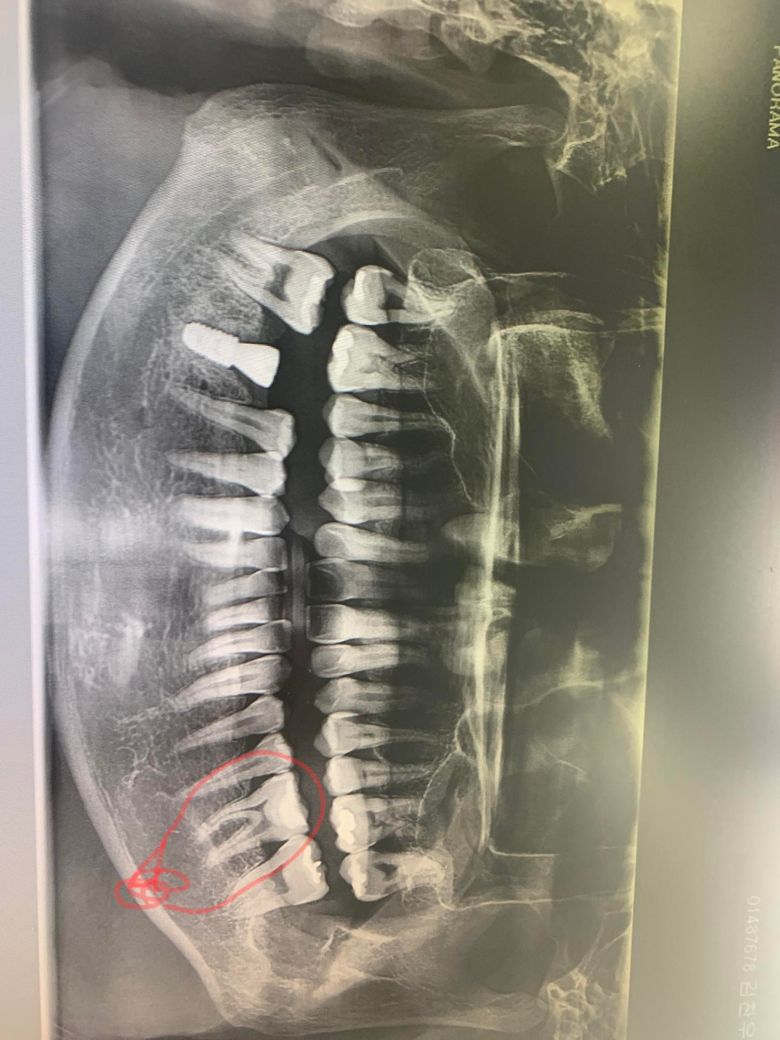

어금니가 평소엔 안아픈데 한번씩 깨같이 작은거 잘못 씹으면 소리를 악 지를정도로 짜릿하고 아파서 차과에 갔는데 금이간것 같아요 그런데 굳이 신경을 다파내고 신경치료를 했어야 하는지 의문입니다. 왜냐하면 의사는 봐도 모르겠다 깨진지도 모르겠다 그랬는데 신경치료안해도 될 이빨을 환자가원하면 신경치료하고 크라운씌워주나요?동그라미친 이빨이에요

해당 치아는 이전에 충치가 심해서 깊게 떼웠던 적이 있습니다. 이런 경우 시간이 지나 치수염이 유발되어 통증이 있을 수 있습니다. 엑스레이 상으로는 특별히 치아 뿌리끝 염증이 아주 심하거나, 크랙이 보이진 않으나 환자 증상에 따라 바로 신경치료를 결정하기도 합니다.

다만, 보통 환자들이 씹을때 느끼는 찌릿한 통증은 위,아래를 헷갈리는 경우도 있습니다. 제가 생각하기엔 아래보다는 위에 어금니들이 문제가 있어보입니다.